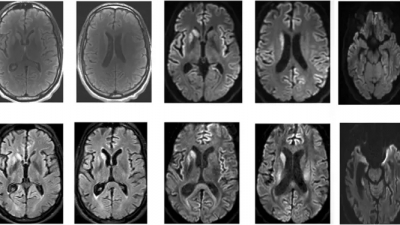

Η σοβαρή μορφή της λοίμωξης που προκαλεί ο κορωνοϊός αφήνει αρκετούς ασθενείς με νοητικές δυσκολίες που μπορούν να συγκριθούν μόνο με τη γήρανση του εγκεφάλου κατά 20 χρόνια, αναφέρουν επιστήμονες από τα Πανεπιστήμια του Cambridge και Imperial.

Η νέα μελέτη για τον κορωνοϊό και τις νοητικές δεξιότητες μετά τη μόλυνση από Covid

Η νέα μελέτη δημοσιεύεται στην ιατρική επιθεώρηση eClinicalMedicine.

Οι ερευνητές υπέβαλλαν σε τεστ νοητικών δεξιοτήτων 46 εθελοντές, τους οποίους είχε νοσήσει βαριά ο κορωνοϊός μεταξύ Μαρτίου και Ιουλίου 2020. Όλοι τους είχαν νοσηλευθεί στο νοσοκομείο.

Όπως έδειξαν οι επιδόσεις των εθελοντών, όσοι είχαν εκδηλώσει τη λοίμωξη που προκαλεί ο κορωνοϊός αντιμετώπιζαν σοβαρή νοητική διαταραχή.

Εκείνη που είχε πληγεί ιδιαιτέρως ήταν η ταχύτητα της γνωστικής επεξεργασίας, δηλαδή της ικανότητας επεξεργασίας των πληροφοριών με αυτόματο τρόπο.

«Οι χειρότερες επιδόσεις παρατηρήθηκαν στην κατανόηση του γραπτού κειμένου», δήλωσε ο επικεφαλής ερευνητής Dr. David Menon, καθηγητής Αναισθησιολογίας στο Cambridge «Δυσκολεύονταν λ.χ. να συμπληρώσουν αναλογίες όπως «τα κορδόνι είναι για τα παπούτσια ό,τι τα κουμπιά για το παλτό»».

Οι διαφορές στις νοητικές δεξιότητες μετά τη λοίμωξη που προκαλεί ο κορωνοϊός, ήταν κάτι παραπάνω από σημαντικές. Κατά μέσον όρο οι ασθενείς είχαν την έκπτωση των νοητικών λειτουργιών που παρατηρείται σε έναν άνθρωπο όταν από τα 50 του χρόνια φτάνει στα 70!

Στη συνέχεια της έρευνάς τους, οι επιστήμονες αξιολόγησαν εκ νέου τους εθελοντές τους στους 10 μήνες μετά την αρχική ανάρρωση. Τα ευρήματα ήταν τα ίδια, αν και υπήρχαν ενδείξεις κάποιας βελτίωσης.

«Τα νοητικά ελλείμματα μετά την σοβαρή COVID-19 σχετίζονται ισχυρά με τη σοβαρότητα της οξείας νόσου», σημειώνουν οι ερευνητές στο άρθρο τους. «Επιμένουν επίσης για μεγάλο χρονικό διάστημα μετά τη χρόνια φάση και υποχωρούν με πολύ αργό ρυθμό, εάν βελτιωθούν καθόλου».